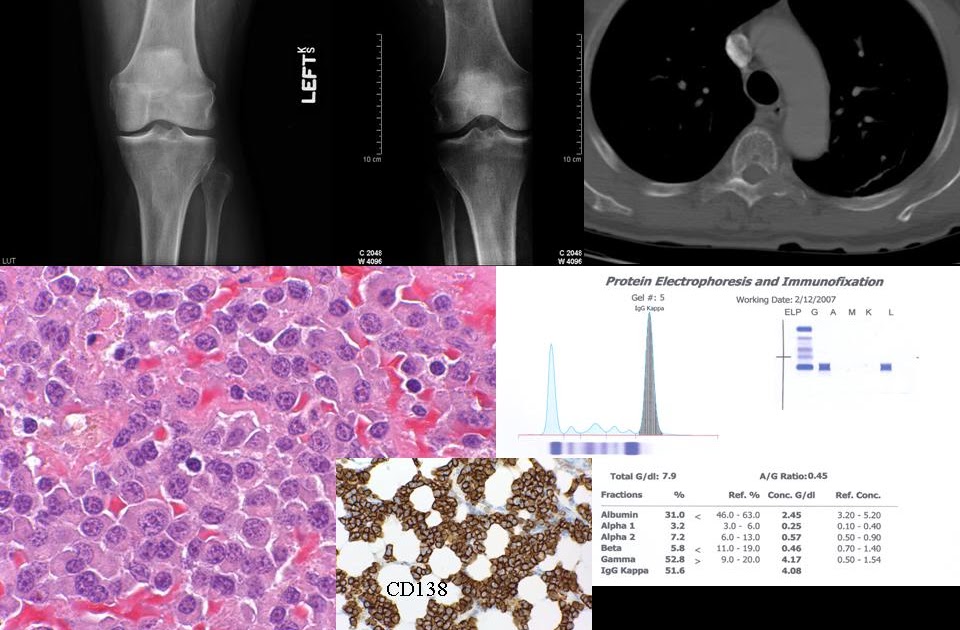

Multiple myeloma differential diagnosis wikidoc